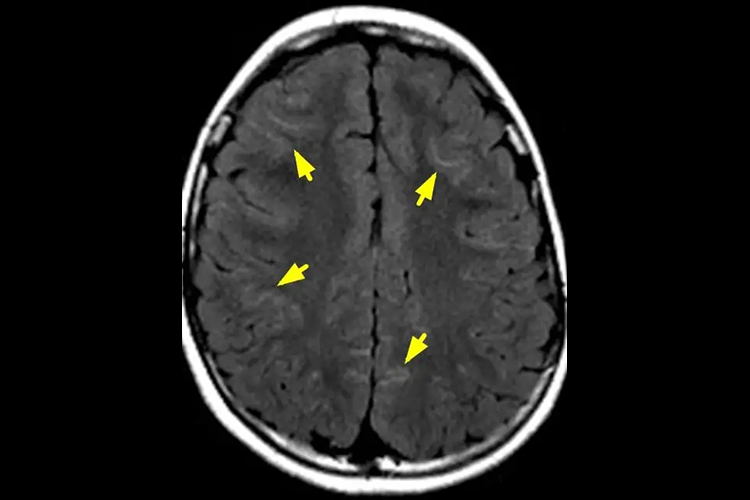

急性期蛛网膜下腔出血MRI显示效果极差,一般不能在MRI上显示。蛛网膜下腔出血数天以后,血红蛋白逐渐氧化成为顺磁性极强的高铁血红蛋白,可使T1明显缩短,在T1WI图像为高信号,对于CT难以显示的亚急性或慢性蛛网膜下腔出血,MRI显示效果较佳。